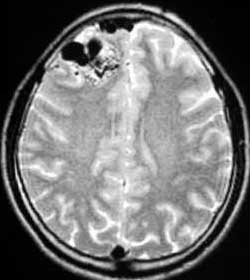

二、脑动静脉畸形(AVM)

---- Spetzler对AVM的分级方法已越来越多地被人们接纳和采用。脑AVM最危险的症状之一是出血。AVM每年的出血率为3%~4%,第一年内再出血约6%。每次出血的致残率为30%,病死率为12.5%,而积极治疗的总残废率加病死率在10%以下。

血管内栓塞对于单支或少数供血动脉的AVM,特别是新近出血的病例,可以达到微侵袭、痛苦小、疗效迅速的目的。

近来改变栓塞方式,将导管直接放置 畸形血管团内,注射NBCA胶,可使畸形团的解剖 治愈率提高至27%。再加上更细、超滑的微导管问世,栓塞的并发症更为降低。针对大型、功能区 的AVM栓 塞可缩小其体积,改善血液动力学分布,以利于显微外科技术切除或放射外科治疗,是后二者的重要辅助手段。